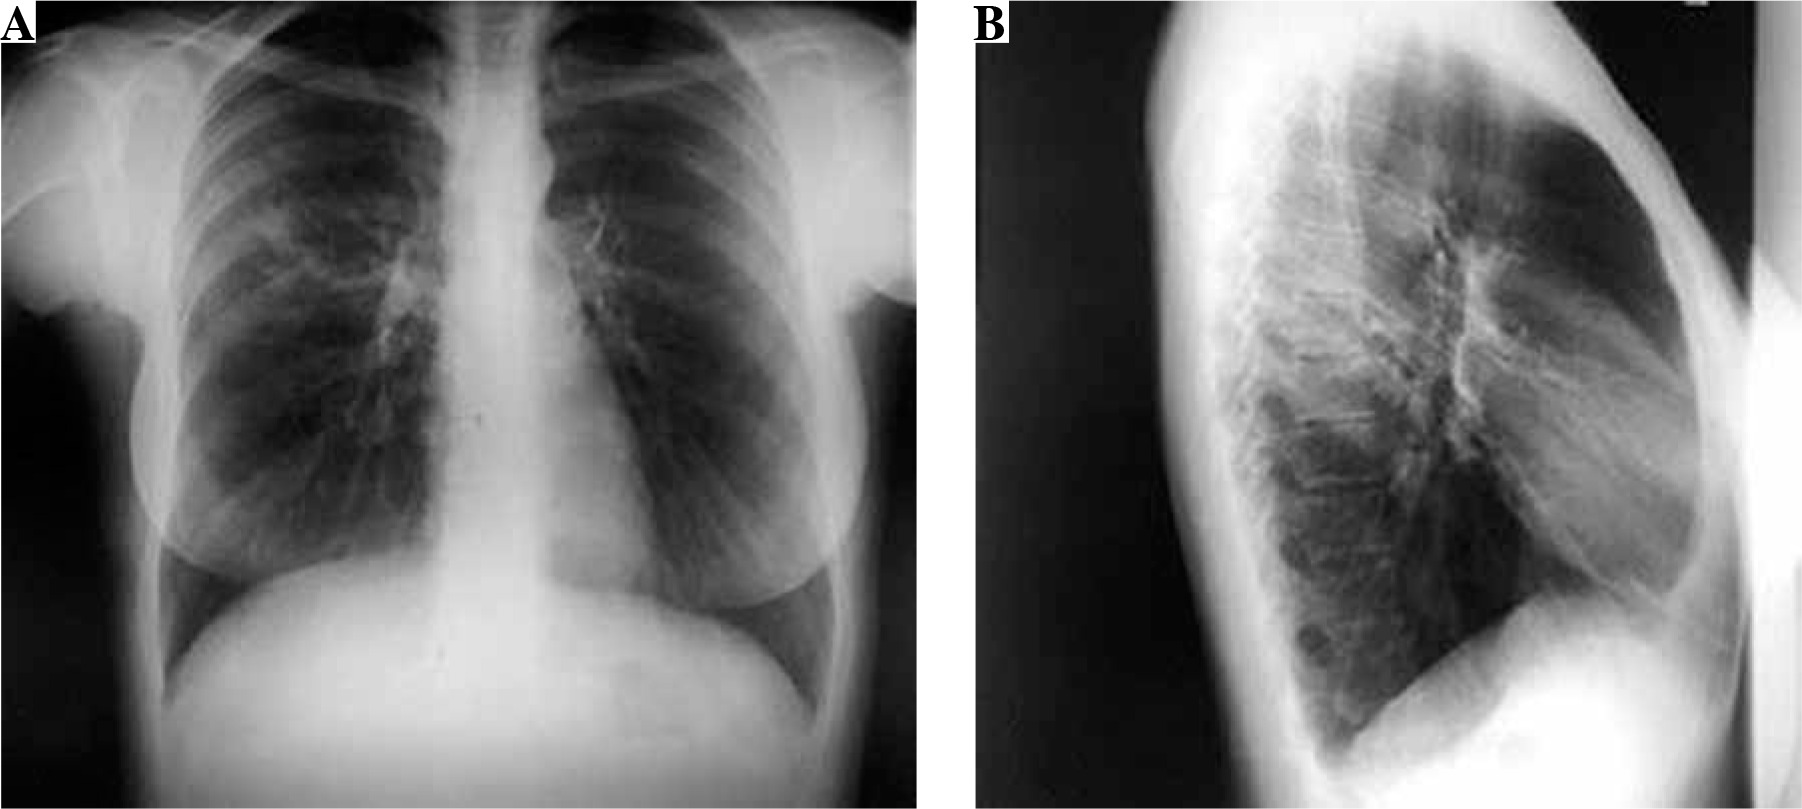

A 31-year-old woman was admitted to the hospital for the treatment of newly diagnosed drug-resistant (pre-extensively drug resistant) pulmonary tuberculosis (chest X-ray at time of diagnosis – Fig. 1). She was treated with second-line antituberculosis drugs: moxifloxacin, kanamycin, cycloserine, prothionamide, para-aminosalicylic acid. After 3 weeks of therapy she developed high fever (> 39°C), lymphadenopathy in the cervical and axillary regions and pruritic maculopapular eruption all over the body (Fig. 2). Hematologic abnormalities such as leukocytosis with eosinophilia (1.81 × 109/l) and monocytosis (1.85 × 109/l) were detected in peripheral blood of the patient. Hepatitis was asymptomatic and detected by the evaluation of liver function: serum aspartate aminotransferase (AST) 1379 IU/l and alanine aminotransferase (ALT) 1221 IU/l; levels of liver enzymes were increased by approximately 30-40-fold above the normal limits. The positive diagnosis of Epstein-Barr infection was based on the onset of increase in the anti-Epstein-Barr immunoglobulin (Ig) G titer (> 200 U/ml), implicating Epstein-Barr virus re-activation. Based on the clinic and laboratory findings diagnosis of DiHS/DRESS was suspected, and all the drugs were discontinued. Symptoms and laboratory abnormalities gradually resolved over 4 weeks without additional treatment.

Fig. 2

Macculopapular exanthema on the patients body after three weeks of second-line treatment for tuberculosis